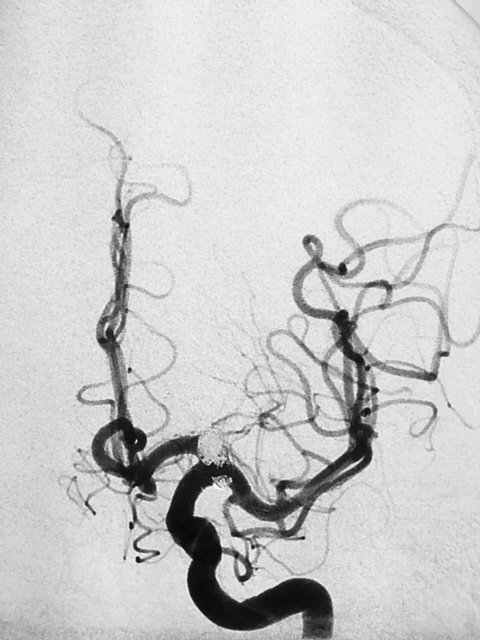

SNA. 76 anos. Durante investigação ambulatorial de cefaléia e tremor nas mãos foi realizado Angiotomografia de crânio evidenciando aneurisma incidental em topo da artéria carótida interna esquerda. Foi realizado Angiografia Cerebral diagnóstica para programação adequada do tipo de abordagem cirúrgica, neste exame confirmou a presença deste aneurisma sacular de contornos irregulares, com orientação superior e anterior, medindo 7,0 x 4,0mm com colo estimado de 4,5mm.

Diante da localização do aneurisma ( intradural ) foi indicado o procedimento terapêutico endovascular. Desde então se programou abordagem com uso de neurostent e molas em virtude da largura do colo do aneurisma. A discussão maior foi em relação ao posicionamento deste stent, direcionando para segmento A1 da artéria cerebral anterior ou segmento M1 da artéria cerebral média. Outros detalhes relevantes, esta paciente apresentava outro baby aneurisma em artéria do complexo comunicante anterior opacificando-se pela artéria carótida interna esquerda, hipoplasia do segmento A1 da artéria cerebral anterior á direita e outro aneurisma de segmento comunicante da artéria carótida interna esquerda.

Ambos posicionados em segmento proximal de artéria carótida interna, com progressão gradativa no Cateter Envoy XB DA 070 para segmento petroso desta mesma artéria. Inicialmente realizou micronavegação  do  aneurisma de segmento comunicantecateter com microcateter Echelon 10 microguia Silver Speed 0,10  e liberado 2 microespiras  posteriormente progredindo até saco aneurismático do aneurisma de topo de carótida. Assim, em sistema coaxial foi progredido microcateter VASCO 21 até o segmento M1 da artéria cerebral média, sendo optado pela orientação do aneurisma e orientação de seu colo com maior envolvimento deste mesmo vaso. Assim, diante do posicionamento adequado de ambos os microcateteres iniciou a liberação controlado do stent LEO, e por seguinte liberado um total de 8 microespiras no saco aneurismático até oclusão completa-Raymond 1.